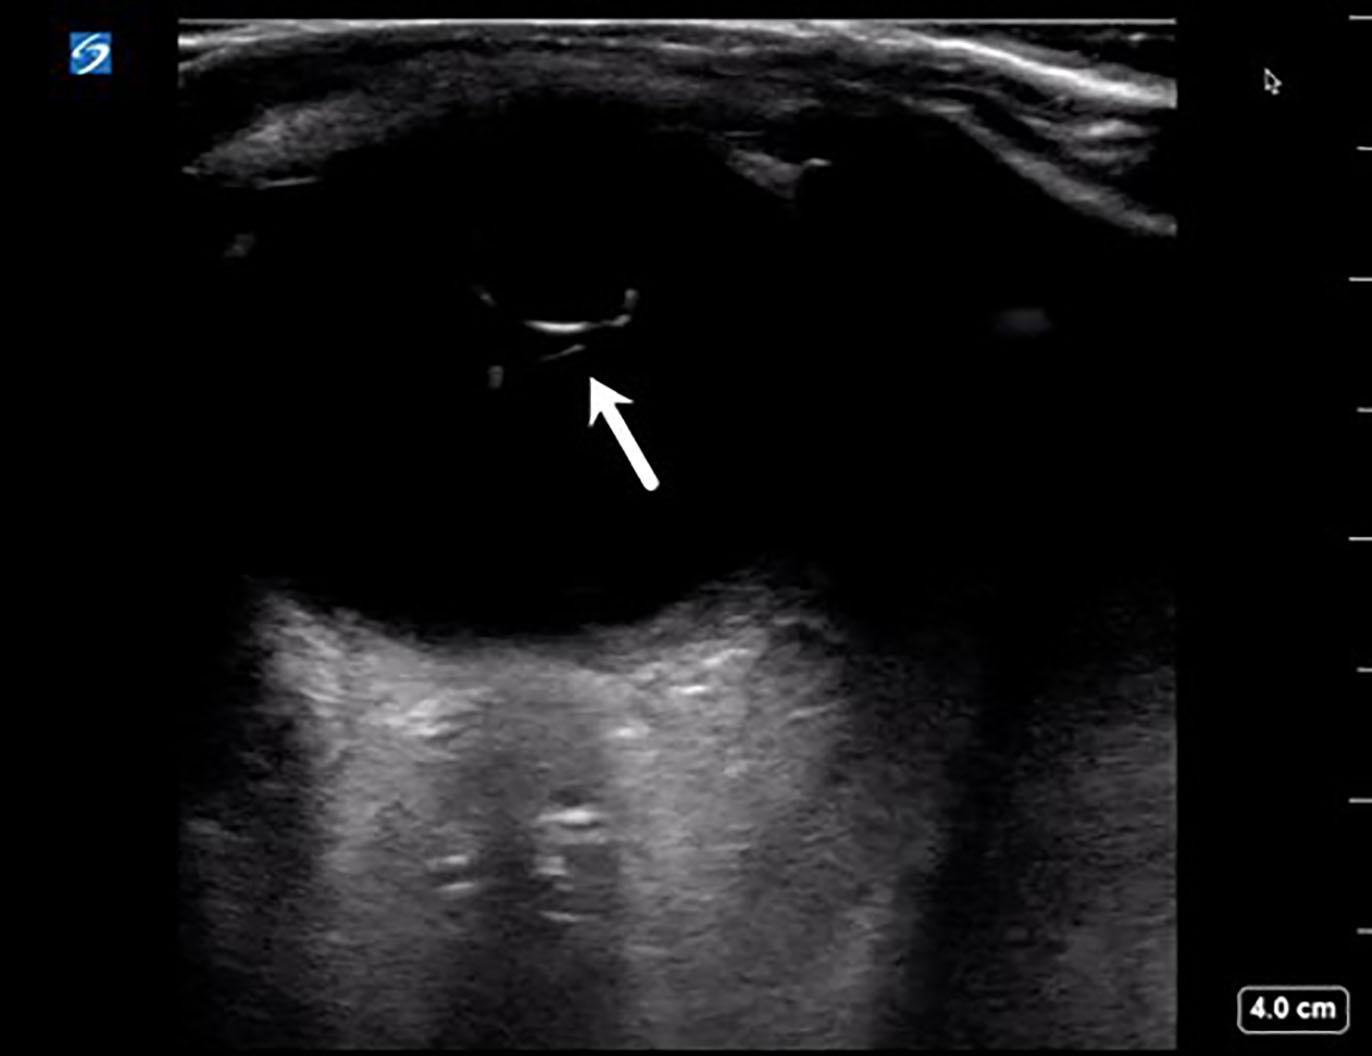

Point-of-care ultrasound of the affected eye was performed in the sagittal and transverse anatomic planes using a high-frequency linear transducer. The prosthetic lens was visualized in the posterior chamber with the temporal side haptic still adherent to the lens capsule consistent with an IOL dislocation (Video, Image), whereas an appropriately positioned prosthetic lens would appear as a hyperechoic curvilinear structure within the lens capsule posterior to the iris. The patient was then asked to perform the six cardinal positions of gaze to maximize visualization of the ocular

Image. Ultrasound image showing intraocular lens dislocation (arrow) into the posterior chamber.

Video. Ultrasound clip showing intraocular lens dislocation (arrow) into the posterior chamber. The prosthetic lens appears as a hyperechoic curvilinear structure in the posterior chamber with the temporal side haptic still adherent to the lens capsule, whereas an appropriately positioned prosthetic lens would appear within the lens capsule posterior to the iris.